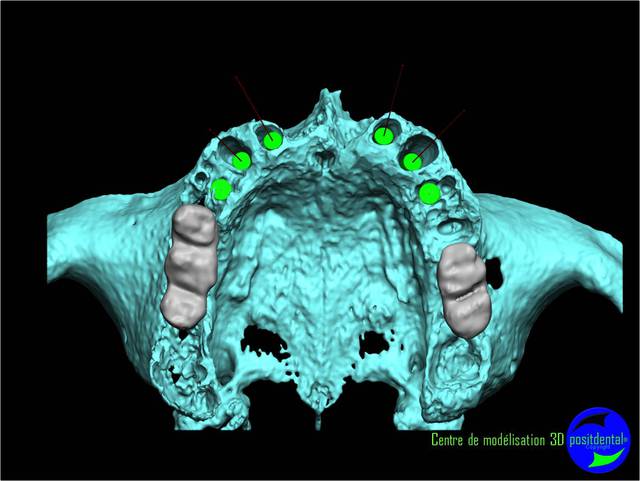

La vidéo présente à partir des plans de traitements, des chirurgies de beotien , des dispositifs médicaux sur mesure positdental et positguide la mise en charge immédiate post-extractionnelle d’un bridge provisoire à armature métal en prothèse fixe sur implants cône morse donc sans vis de maintien. Une question est émise « comment obtient-on ce résultat ? ». Une partie des réponses comme la prédictibilité, la reproductibilité peuvent y être déduite pour d’autre il faudra la bonté de beotien de faire partager les résultats clinique.il nous fait la générosité de poster la phase cicatriciel à 7 jours et des photos de la chirurgie sur un cas.

planif cas 1

Si tu as suivi les cas présentés depuis plusieurs années les bridges provisoires ont une armature métal pour la rigidité du fixateur externe, l’intervention se déroule en 1 seul temps chirurgical donc sans prise d’empreinte, c’est pour cela que je parle de MCI. Pour la passivité du bridge avec le système Nobel Guide et leurs piliers expansifs je n’ai vue aucun cas clinique présenté sur le forum. As-tu déjà utilisé le procédé ? Dans les cas présentés sur la vidéo, aucune clé de positionnement n’a été utilisée, le placement des piliers se fait selon la simulation implantaire assistée par ordinateur, leurs présentations a été faite en prospective par OTP, modèle 3D et à la demande de beotien la solution pilier fixe a été retenu à la place du bridge transvisé. Quel sont les compléments d’information que tu as besoin et ou la photo ne te suffi pas ? Pour le protocole d’une MCI, empreintes des maxillaires, dimension verticale de l’occlusion, définition de l’esthétique souhaitée, prescriptions, réalisation du Positscan, traitement des informations à partir des données DICOM, simulation implantaire assistée par ordinateur, validation, réception des DMSM selon les types d’implants et encastillages les procédures varient. Quel système implantaire utilise-tu ?